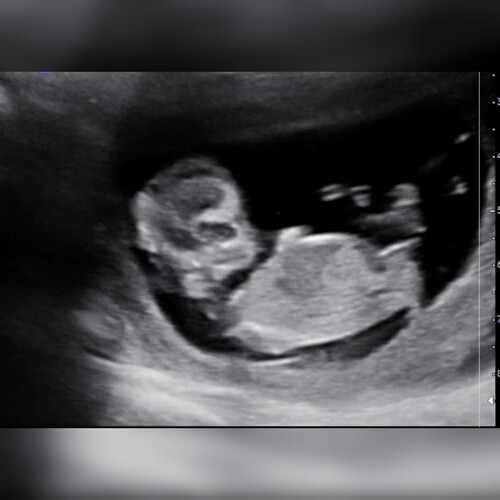

Net de 13 weken echo gehad op 13 + 1. We zijn ontzettend benieuwd of iemand al kan zien wat het geslacht is/wordt! ☺️

Net de 13 weken echo gehad op 13 + 1. We zijn ontzettend benieuwd of iemand ...

Haha nogmaals dan: 💙

Ik heb nog wel meer echo foto’s maar ze zijn allemaal wat wazig doordat de placenta aan mijn buikzijde zit

Meer foto's niet nodig hoor, tis duidelijk